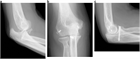

1. 肘関節不安定性が持続する慢性靭帯損傷では、靭帯再建術を行うことが推奨される。